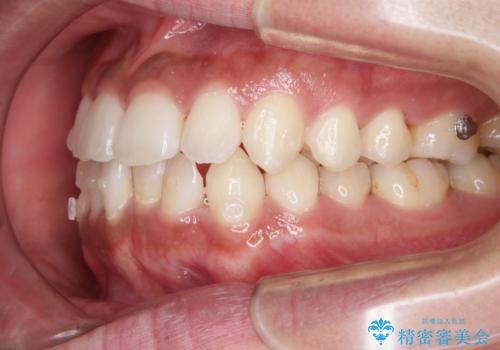

- 上下の前歯のがたつきが気になるとご相談にいらした方です。光加速矯正装置(オルソパルス)を用いて短期間で仕上げることが出来ました。

一般的に噛む力が強い方は矯正治療に時間がかかると言われてます。光加速矯正装置(オルソパルス)を用いることで短期間で仕上げることができました。